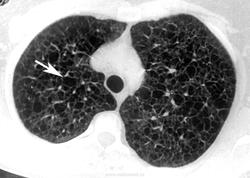

лимфангиолейомиоматоз

Типичный пример патологии при которой основным патерном являются кисты - :

Лимфангиомиоматоз.

Из архива AFIP. Лимфангиолейомиоматоз.

ЛАМ'ом болеют женщины.